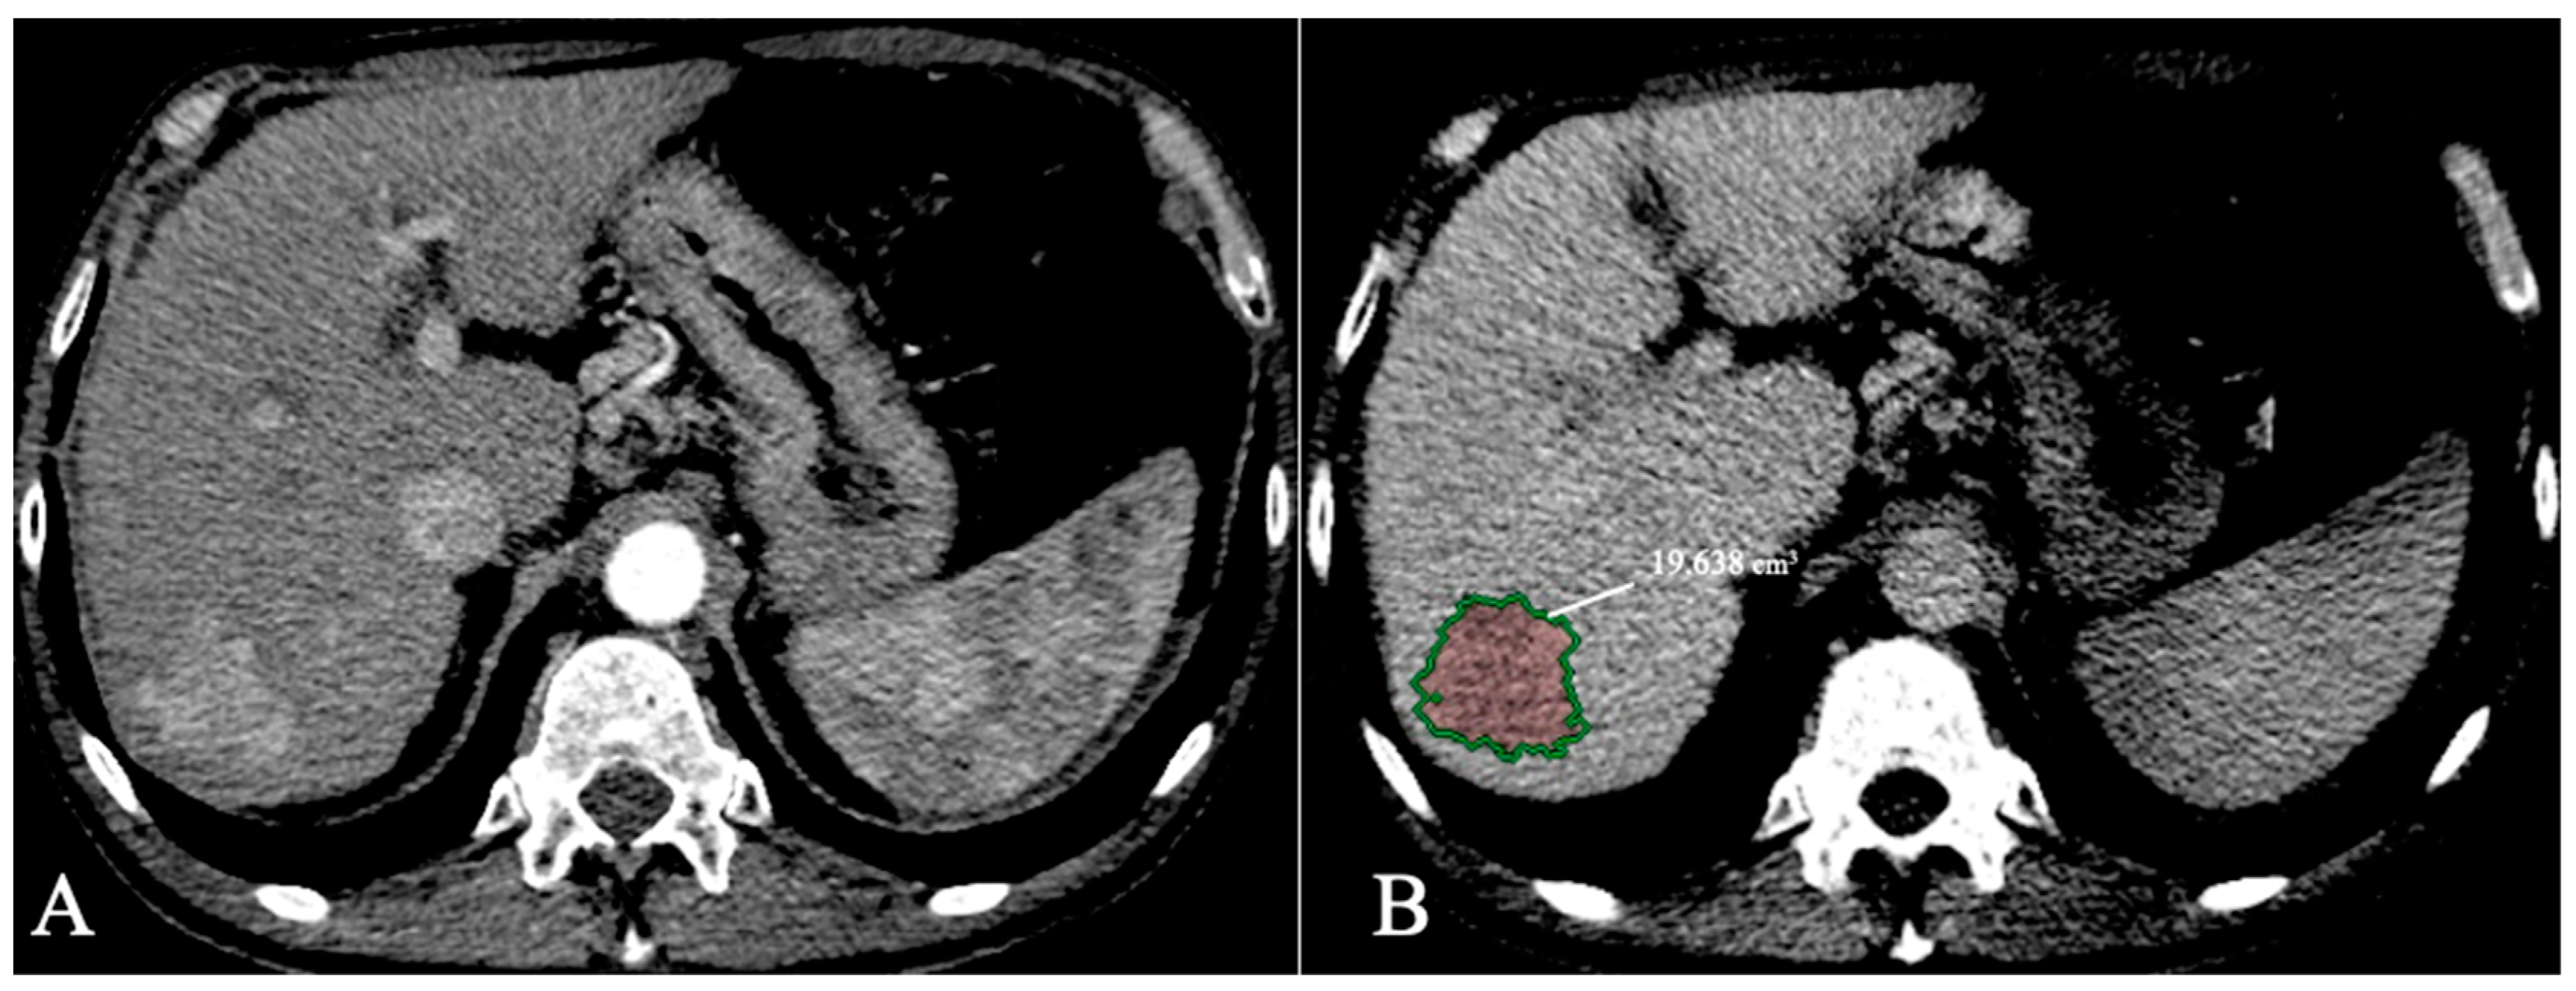

- Bousabarah, K.; Letzen, B.; Tefera, J.; Savic, L.; Schobert, I.; Schlachter, T.; Lin, M. Automated detection and delineation of hepatocellular carcinoma on multiphasic contrast-enhanced MRI using deep learning. Abdominal Radiology 2021, 46, 216–225. [Google Scholar] [CrossRef] [PubMed]

| Bousabarah et al. [70] | 2021 | Liver and HCC segmentation | MRI | DL | 91% for liver 68% for HCC |